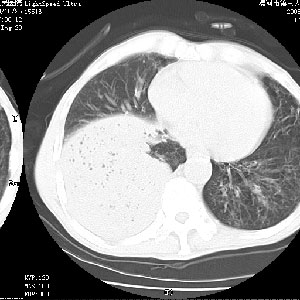

考虑为右肺下叶支气管痰栓形成并阻塞性肺不张及肺炎。

按肺叶分布,考虑肺不张

考虑:阻塞性肺炎伴小脓肿形成可能性大。(痰栓可能性大)

右下肺阻塞性炎症,内见多发气体影,以肺叶分布.不支持不张.